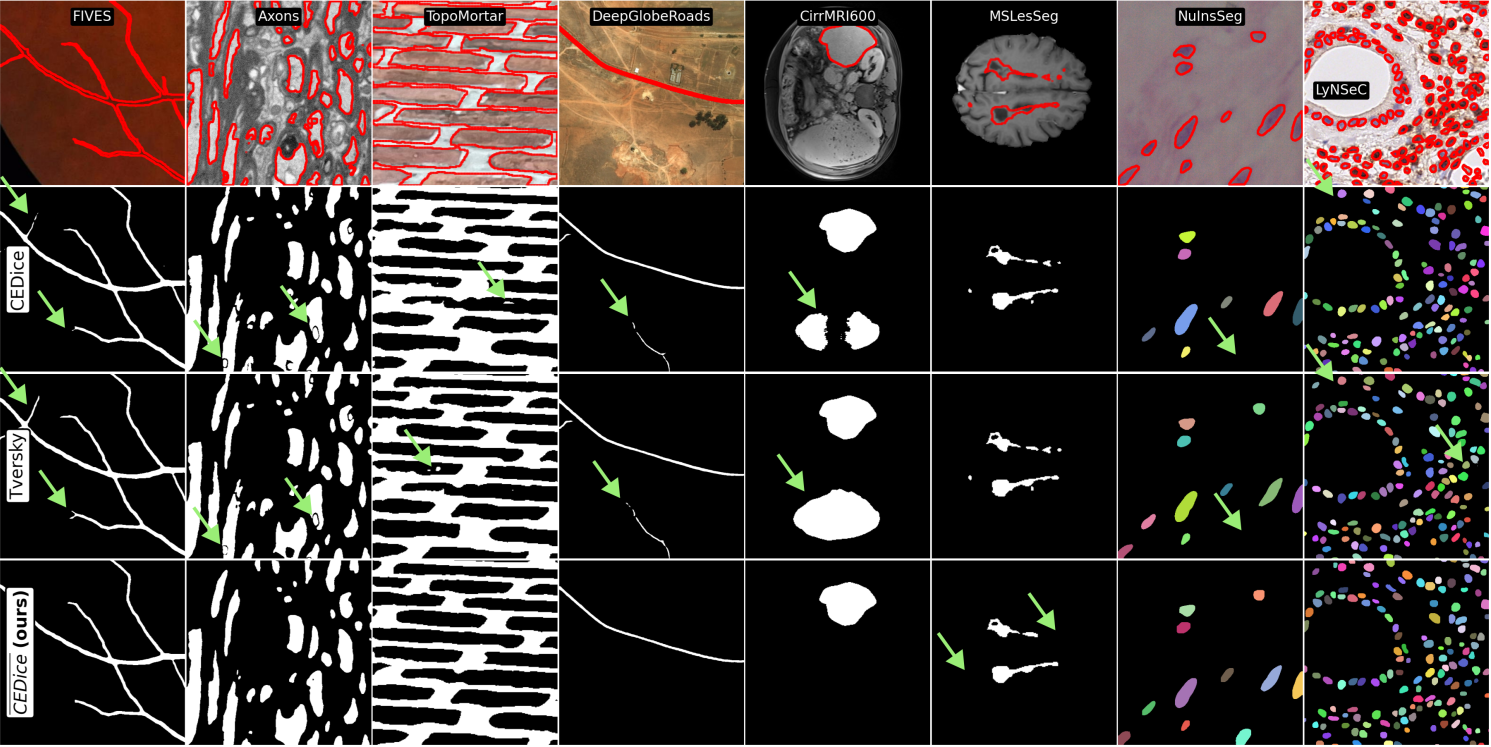

Qualitative results.